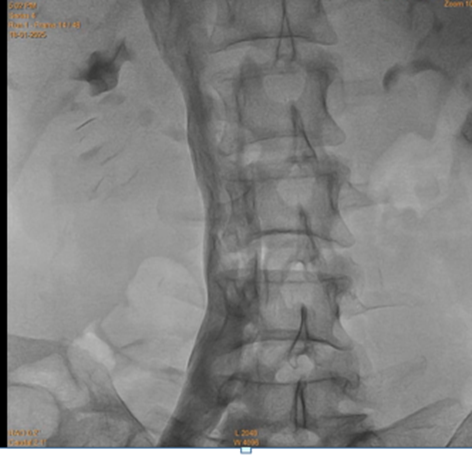

Keeping in view the possibility of Nutcracker syndrome (NKS). patient was taken up for percutaneous treatment. Right femoral vein puncture was done. Femoral vein angiography was done to see inferior vena cava (IVC), (Fig.1) to have idea of origin of left renal vein. Femoral artery access was also taken and left renal arteriography was done to trace renal vein in venous phase, but it could not be visualised. Since renal vein was not visualised, blind entry was done with terumo wire passed through right Judkins (JR)catheter. Catheter was then negotiated into LRV and venography was done (Fig. 2). It showed markedly dilated left gonadal vein (LGV), and left ovarion vein (Fig 3). Hardly any contrast was entering into IVC, due to compression by superior mesenteric artery (SMA). It was decided to put a stent in LRV across the compressed segment. To properly define the site of obstruction and stent placement, a JR catheter was placed in SMA (Fig 4), from left brachial artery approach. Self-expanding venous stent was then deployed, size 14x 60 mm. (Fig 5). LRV angio was then done which showed free flow of contrast into IVC and minimal reflux into LGV (Fig. 6). If, large reflux persisted, then coiling of LGV would have been required.

Figure 1: Inferior veno-cavography